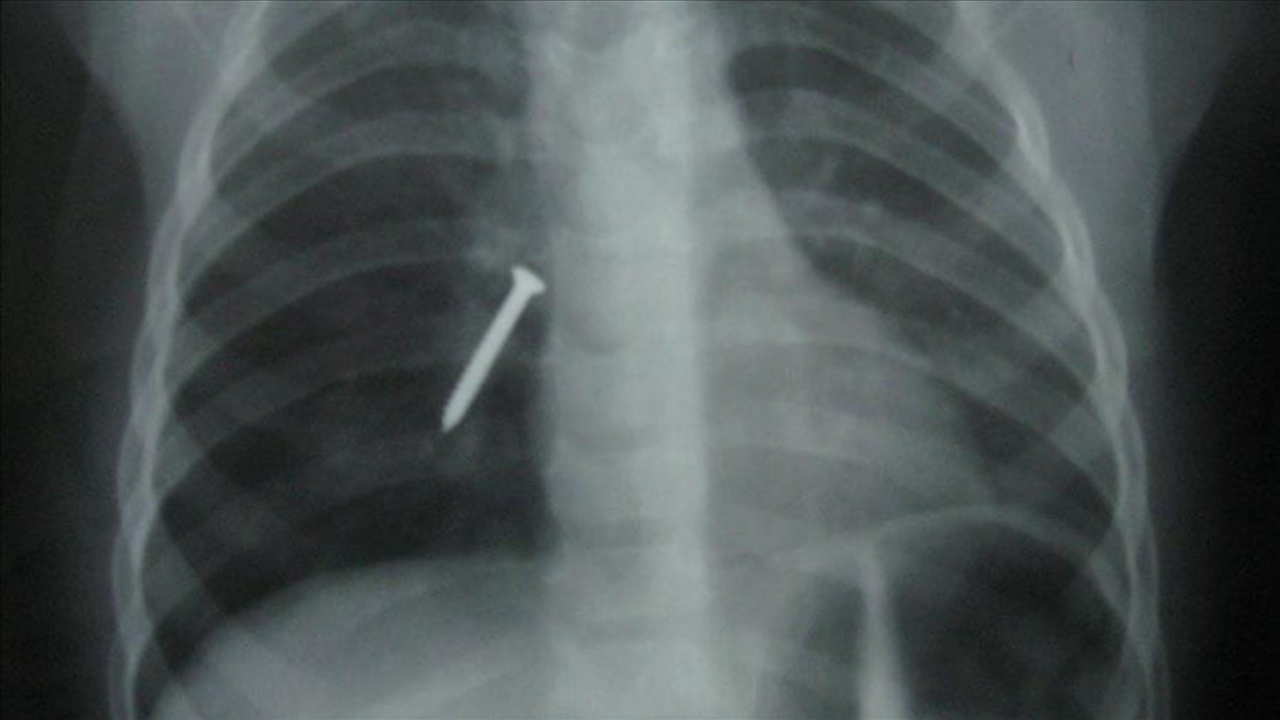

Radyolojik inceleme sonucunda yaklaşık 4 santimetre uzunluğundaki çivinin mideye ulaştığı tespit edildi. Uzman doktorlar tarafından gerçekleştirilen endoskopik müdahalede, çivi herhangi bir komplikasyona neden olmadan başarıyla çıkarıldı.